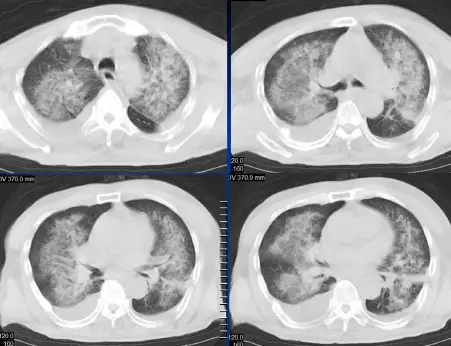

病例:男,28岁,溺水肺水肿,溺水1小时,咳嗽,呼吸困难,咳粉红色泡沫样痰,肺部听诊大量湿啰音。

CT表现

肺泡性肺水肿:两肺透光度减低,并见广泛性分布结节样、斑片样密度增高影及毛玻璃样影,以两肺内、中带分布较明显,右侧较左侧多。